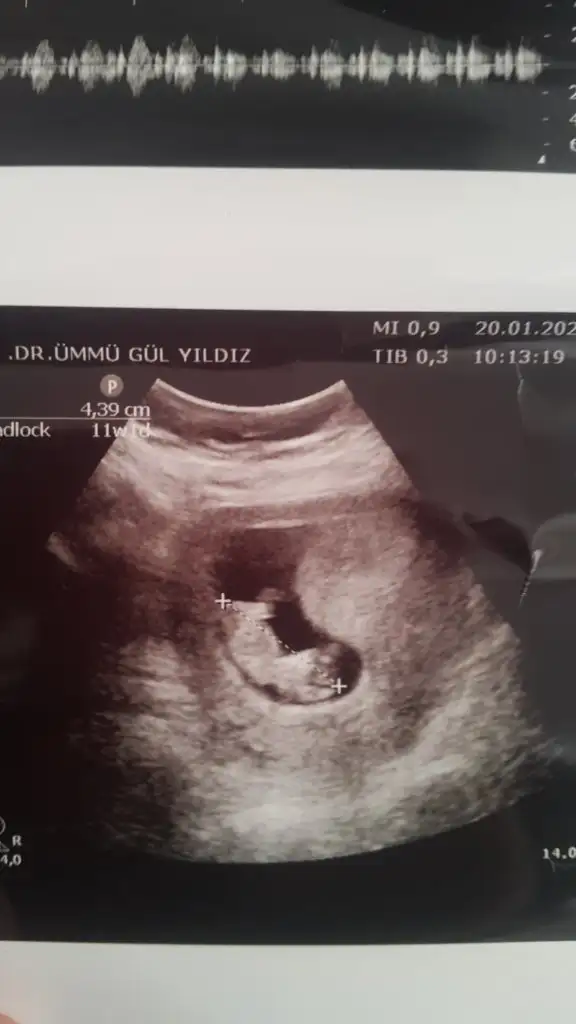

dr soylemeden siz gorun genital nub teorisi ( bebegin cinsiyeti)

Screenshot_20200120-154357.webp

mrhaba lütfen yorumlarmisiniz sizce kızmı erkekmi bi arkadas icin soruyorum